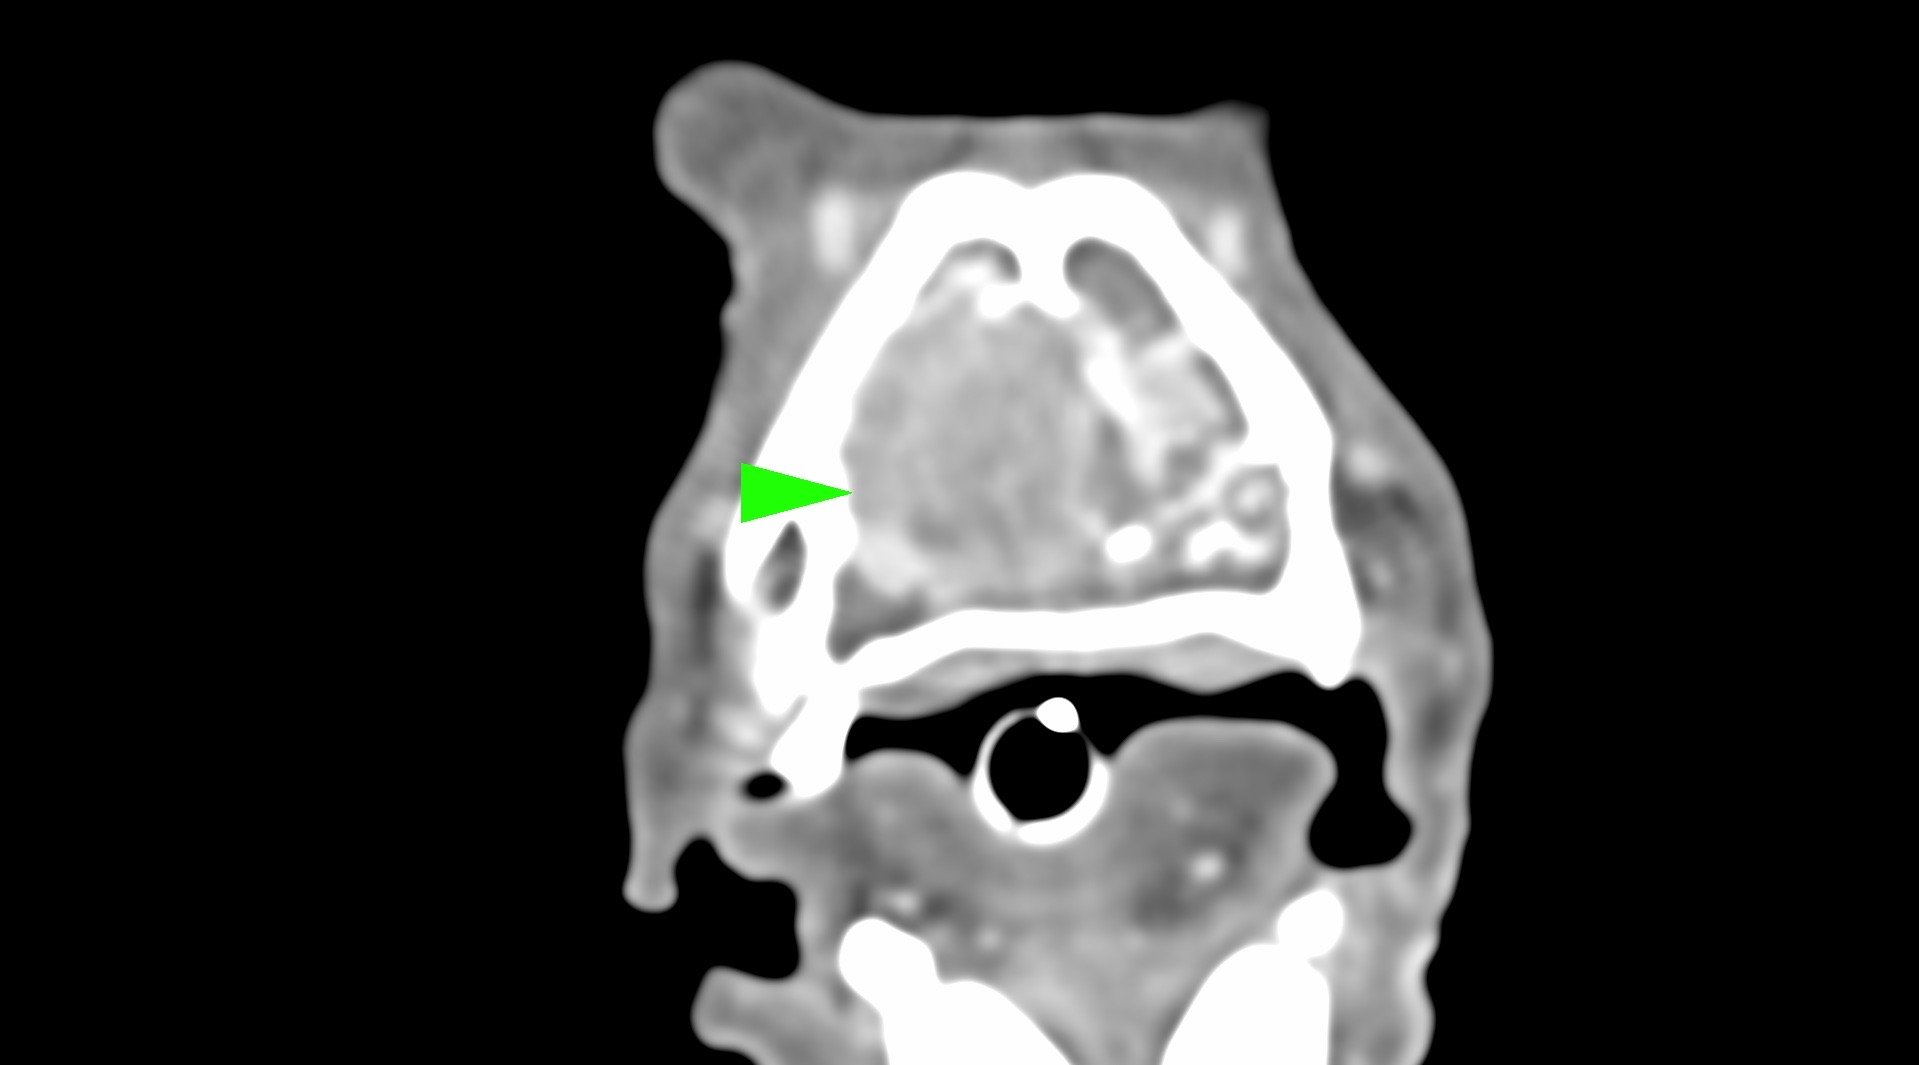

柴犬皮皮因長期有鼻塞、流鼻血、流鼻水的症狀來築心就診,在這之前已經換過兩間醫院,但治療效果都不太好。在一系列的評估後,我們為皮皮安排了電腦斷層以及鼻腔內視鏡的檢查,檢查後發現在皮皮的鼻腔內有疑似腫瘤的團塊,並且向後侵入鼻竇,甚至已經接近大腦。我們運用內視鏡設備採樣取得了團塊的切片,並得到鼻上皮細胞癌的診斷。